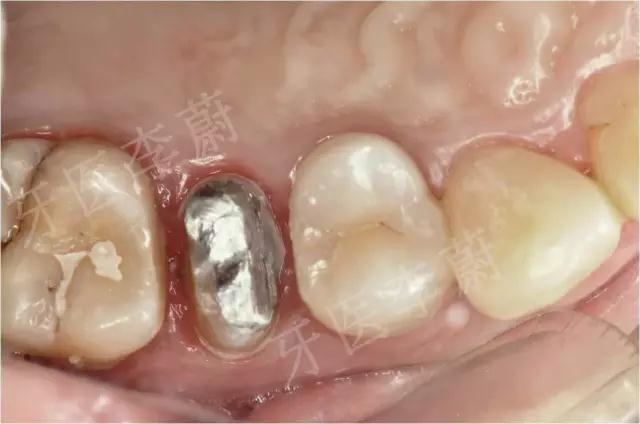

口腔检查:15冠部龋损,探及大量腐质,舌侧冠折至龈下约2mm,近、远中壁亦部分龋坏,松动Ⅰ°,叩痛(-) ,牙龈无瘘管,舌侧及近中被龈组织覆盖。

15牙金属分裂桩口内粘接

15牙冠制备中